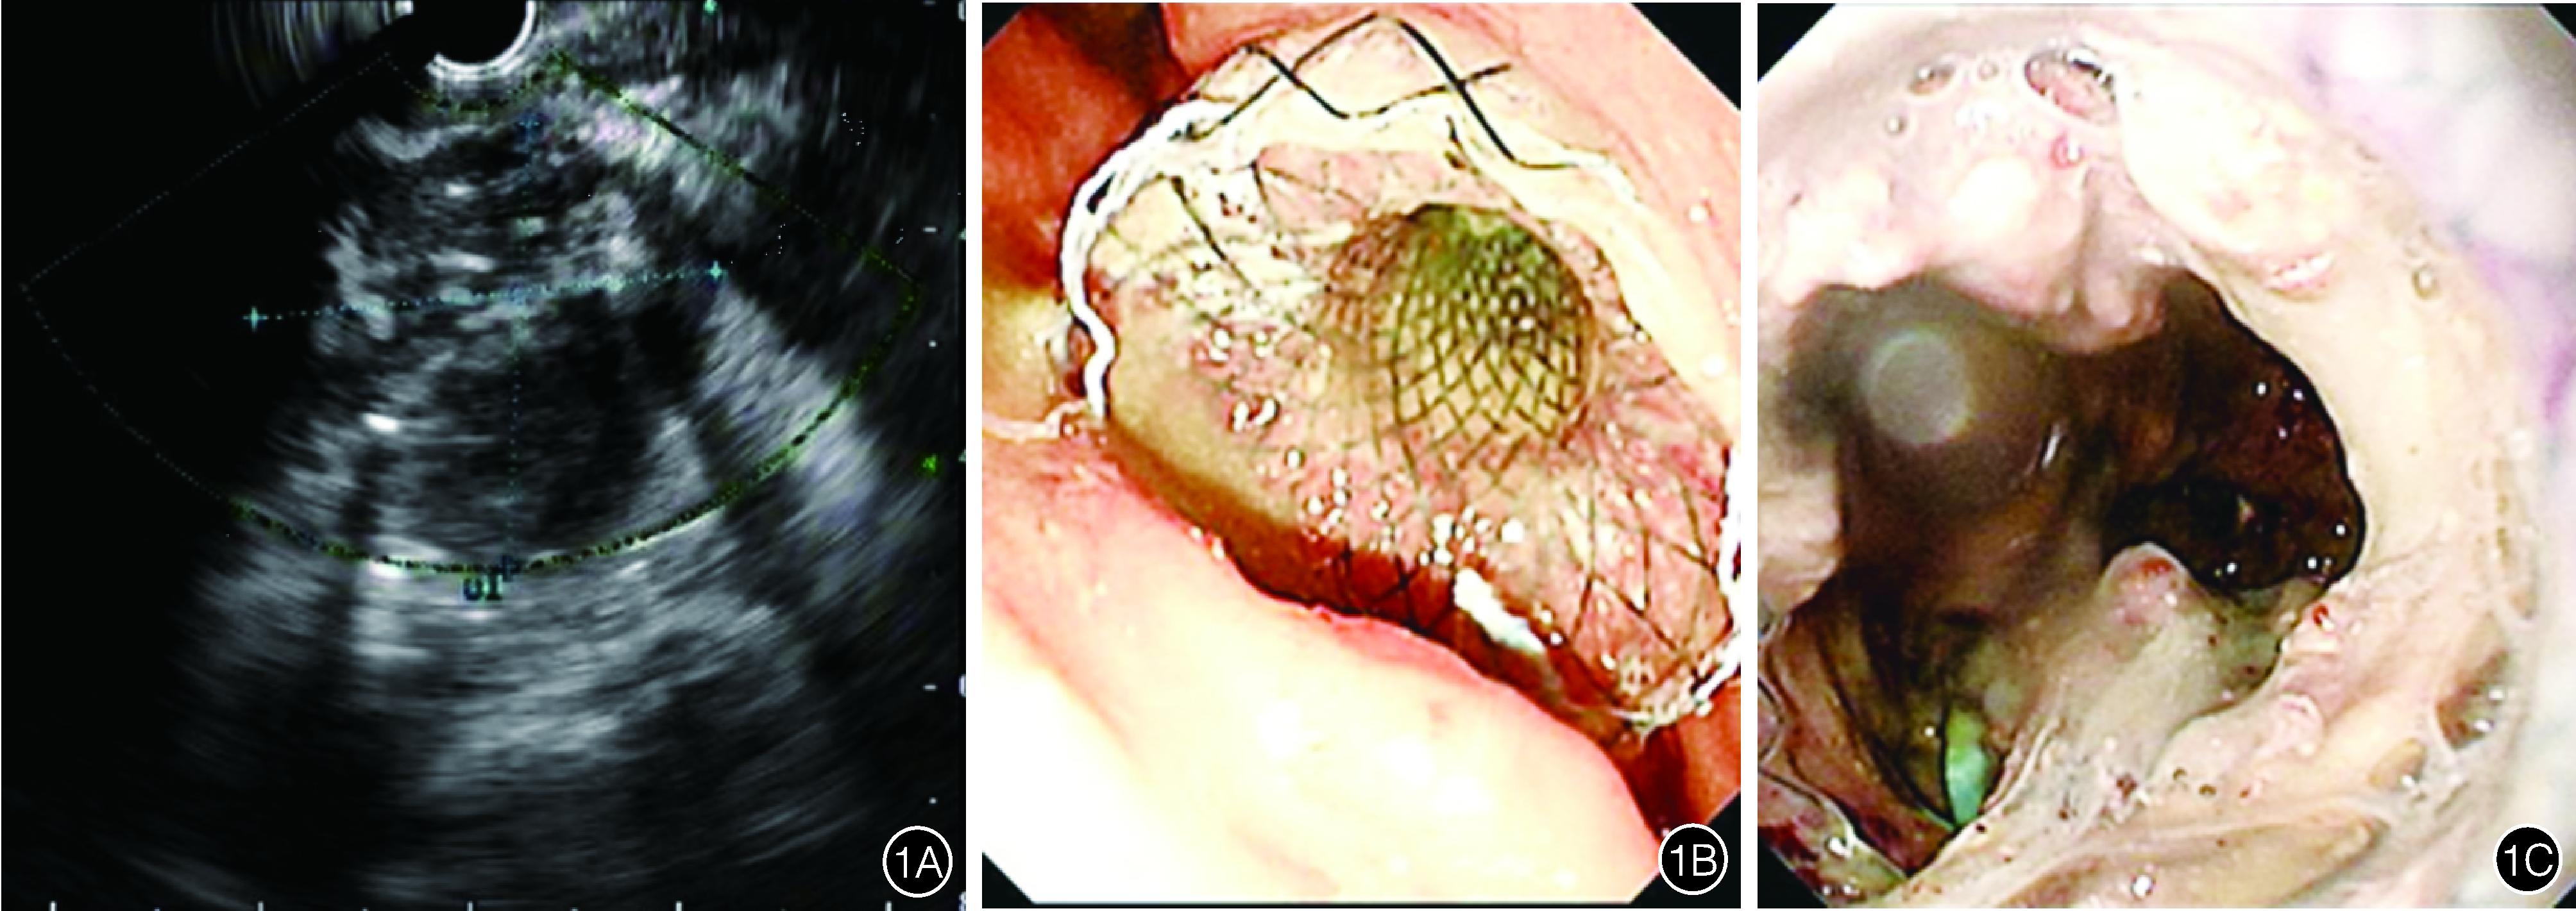

ETD治疗:患者取侧卧位,在全身麻醉下,超声内镜经口插入胃腔,在胃内探查IPN的位置、大小、与胃壁间的距离,在多普勒信号指引下,选择适当穿刺点,以19 G穿刺针穿刺至脓腔内,见脓液流出后,循穿刺针置入导丝,循导丝置入扩张球囊或扩张烧灼导管,扩张后经导丝置入双腔固定支架/金属覆膜支架/双猪尾塑料支架,同时放置鼻囊肿管,支架选择依据IPN内坏死物的多少,对坏死物较少的IPN选择塑料支架,而对坏死物较多的则选择金属支架。金属支架中双腔固定支架或金属覆膜支架的选择则依赖于术者的习惯。术后留取标本送检常规、生化、病原学检查。术后用生理盐水经鼻囊肿引流管对囊腔进行冲洗。术后2周复查CT评估疗效,临床症状改善不明显者,或复查CT感染腔最大径缩小<1/2者行ETN。患者取侧卧位,胃镜经口进镜至胃腔,在胃壁内探查到支架所在部位,内镜循开口处进入脓腔,予圈套器清除坏死物质,生理盐水反复冲洗脓腔。可根据病情需要多次行ETN治疗(图1)。

图1 超声内镜下经胃穿刺支架引流及坏死组织清除术 1A:超声内镜下见距离胃壁小于1 cm的感染性胰腺坏死,有明确的炎性壁,内含坏死物质; 1B:内镜下见双腔固定支架置入胃壁; 1C:内镜下见囊腔内大量坏死物质,经金属支架行清创治疗